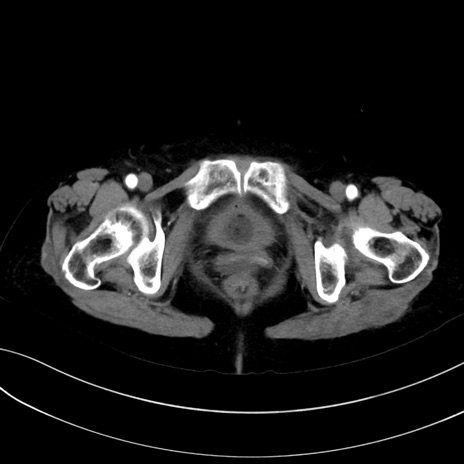

症例13 CT(横断像)1日半後